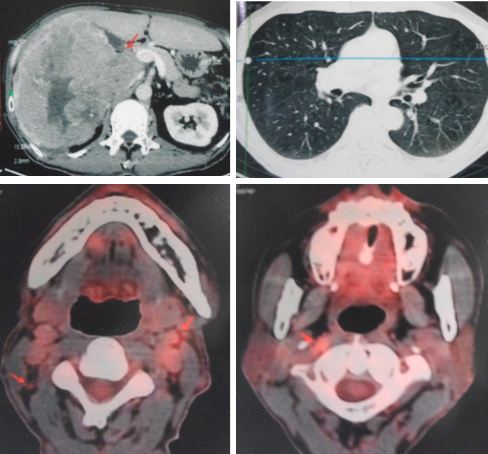

A CT scan showed:

A triphasic CT scan of liver done in July 2015 confirmed:

- Irregular liver surface. Hypodense lesions are seen at both liver lobes, the largest is at segment 7 measures 1.2 cm. These lesions not enhanced in all CT phases.

Fast forward to April 2018 – a repeat Triphasic CT scan showed:

- A solitary non-enchancing homogenous isodense liver nodule 3.3 x 3.6 cm. In view of underlying chronic hepatitis carrier, need to exclude atypical hepatocellular carcinoma.

- Associated underlying liver cysts and haemangioma.

A follow up CT in July 2020 showed:

- Increasing size and number of liver lesions in segment 2 and 3.

- Lung nodules with pleural-based lesions suggestive of lung and pleural metastases.

- Prostatomegaly with chronic bladder obstruction.